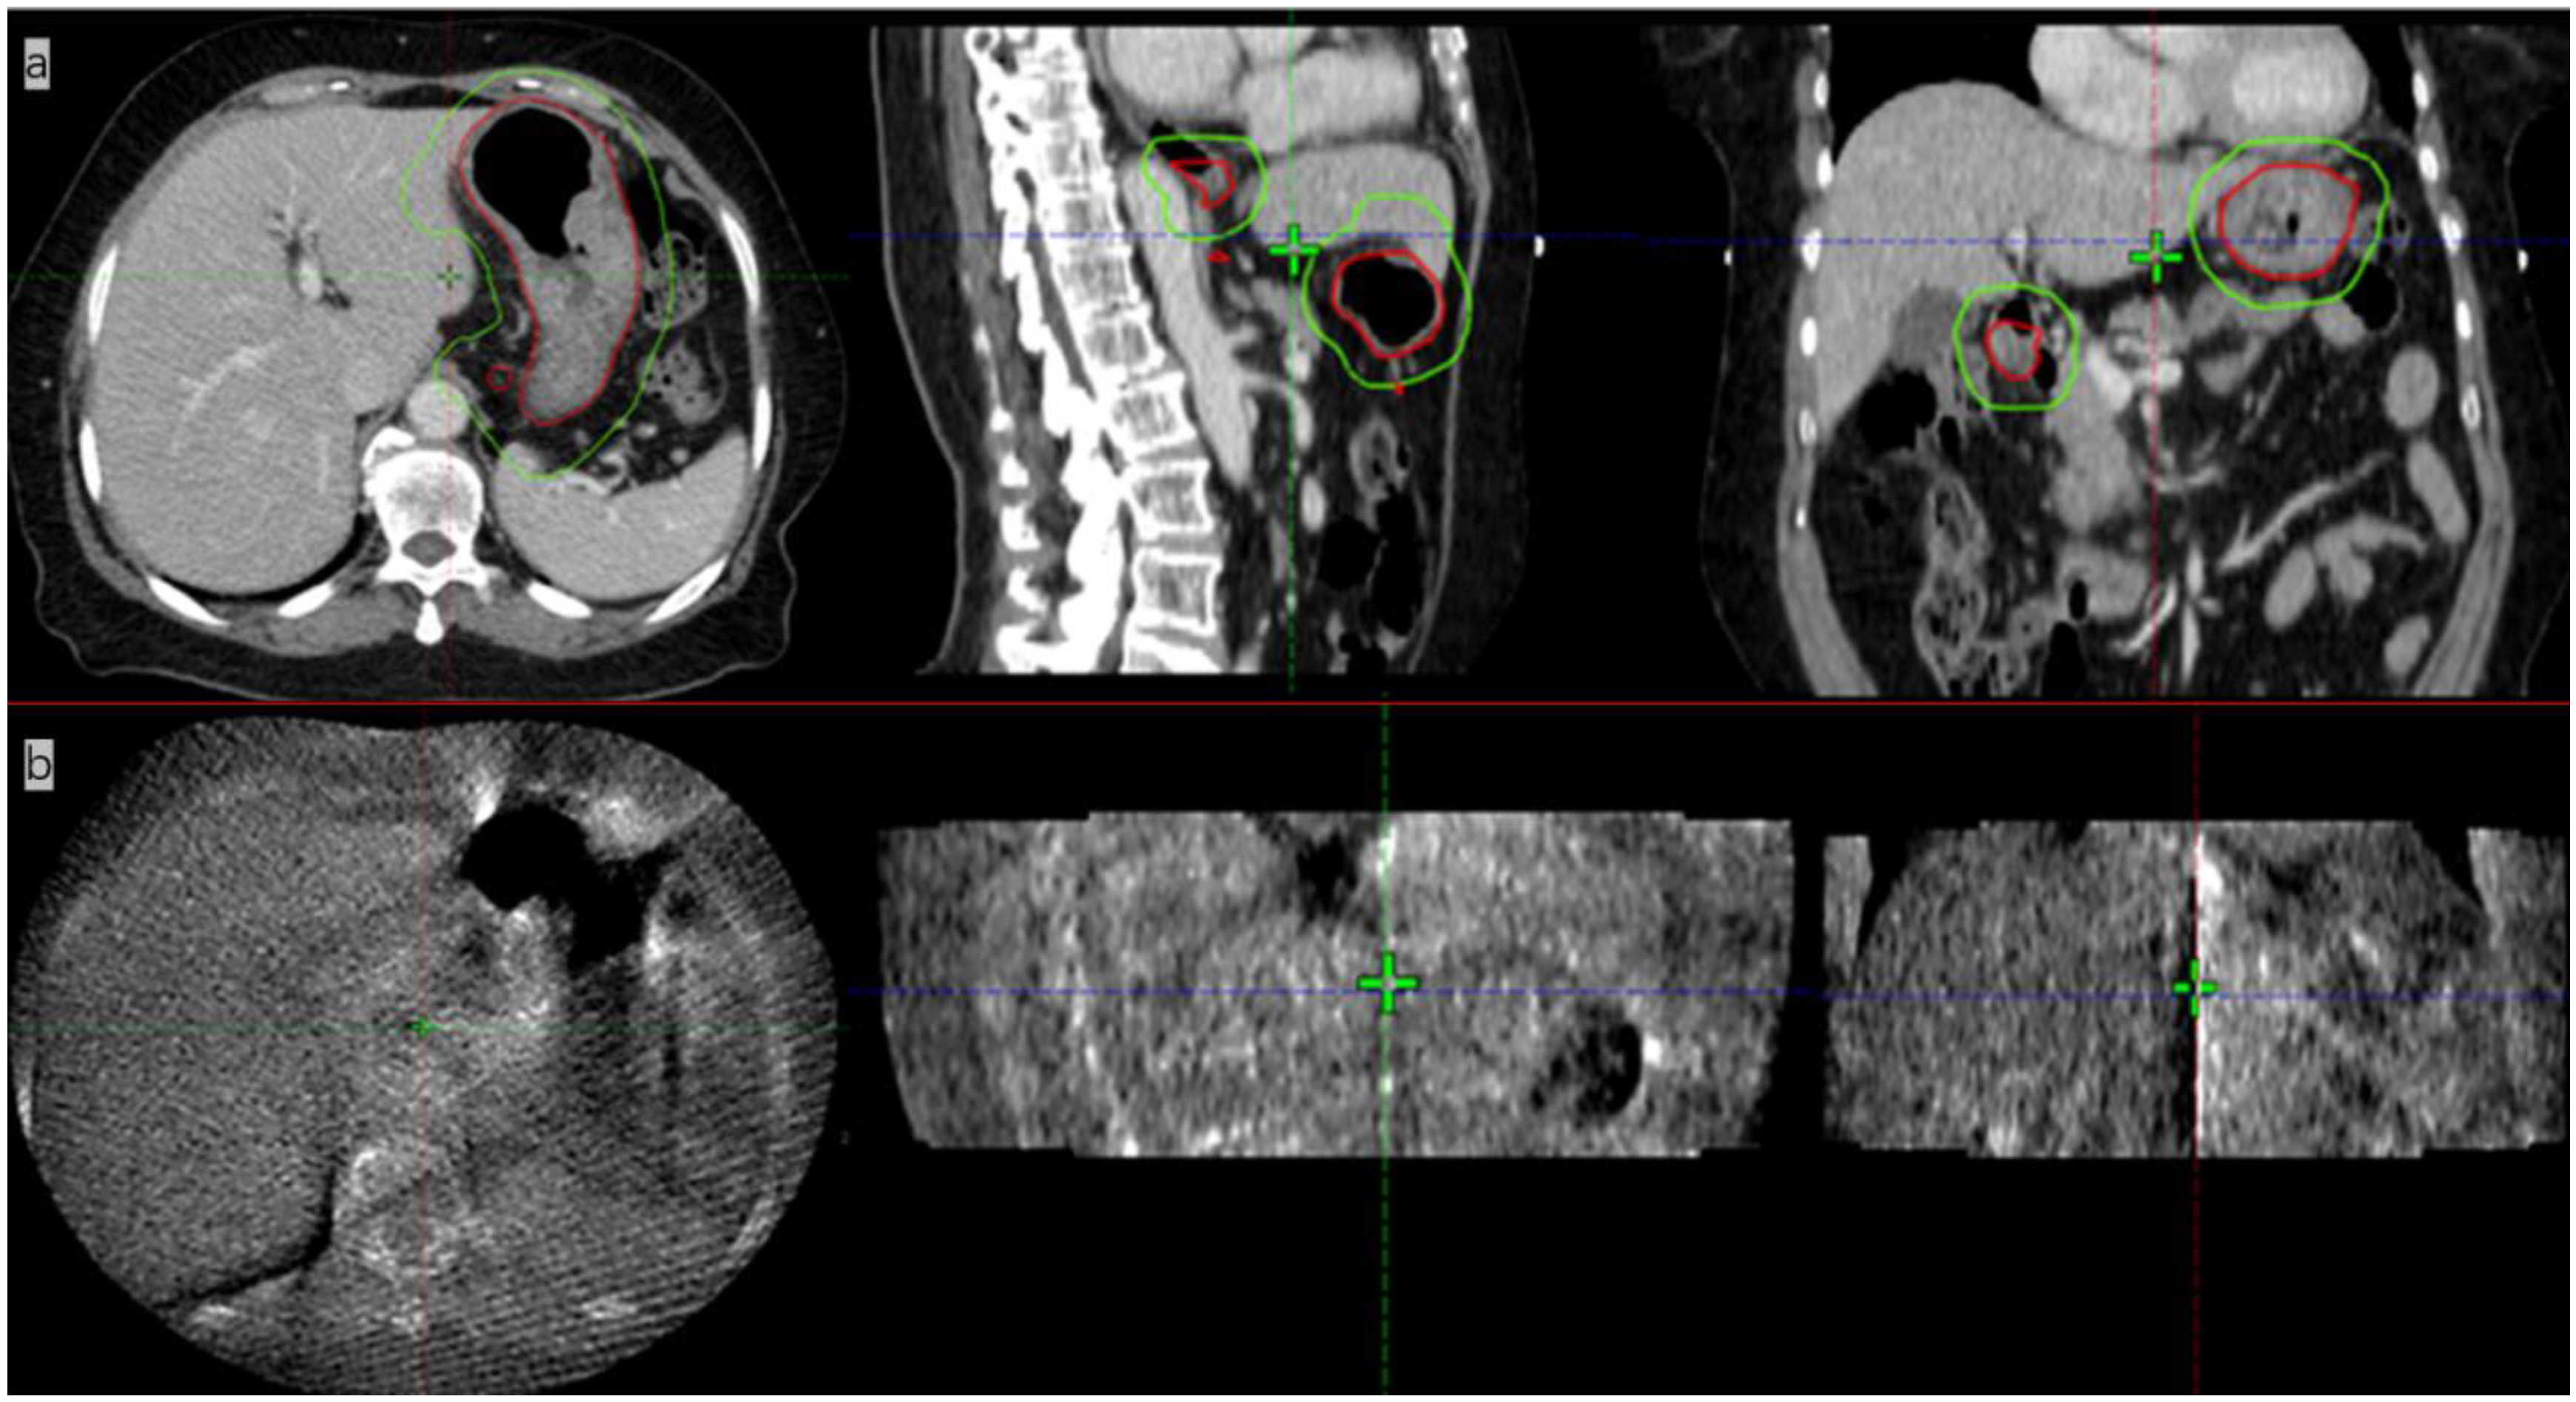

A 53-year-old male patient with a history of gastric bleeding and gastric ulcer for more than 18 years was selected for this study. The patient developed melena on 13 January 2022, without obvious causes. Contrast CT of the chest, abdomen, and pelvis showed that the wall of the gastric antrum was thick with two enlarged lymph nodes. Fluorodeoxyglucose positron emission tomography/CT (FDG-PET/CT) images revealed high FDG uptake in both the gastric wall of the inhomogeneously thickened greater curvature and the two enlarged lymph nodes. Pathological reports presented mucosa-associated lymphoid tissue (MALT) lymphoma in the greater curvature at the junction of the astral body, after performing immunohistochemistry of CD20+, CD43+, CD3+, BCL2+, CD5 minority+, CD23 minority-, CD38 minority+, CyclinD1 minority+, Lambda individual+, BCL-6-, Kappa-, Ki-67+10%. The patient was diagnosed with stage IIE gastric MALT lymphoma according to Ann Arbor staging. The patient received four cycles of rituximab, 600 mg, and then involved site radiation therapy (ISRT) on the whole stomach. The patient underwent a 4D CT scan on an empty stomach. Before the CT simulation, anisodamine (dose, 10 mg) was administered to reduce gastric motility. The entire stomach (clinic target volume, CTV) was delineated in the 4D CT scans, and the images were combined into an internal CTV (iCTV). The combined iCTV included the enlarged metastatic lymph nodes and the planning target volume (PTV), which presented a 5 mm external expansion from iCTV. The patient was treated with ISRT at 30 Gy in 15 fractions. Then, the patient was treated with the Unity MR-LINAC. Prior to each radiotherapy fraction, the patient was kept on an empty stomach and was administered anisodamine (dose of 10 mg). The empty stomach was delineated with automated segmentation using the AI technique, and then the resulting image was reviewed and modified by an attending radiation oncologist. The MRI image of the whole stomach after anisodamine administration was clearer than the images taken without administering the drug (Figure 1). The images obtained with the AI technology using deep learning algorithms showed that the delineation accuracy of the whole stomach gradually improved. The Dice similarity coefficient (DSC) increased gradually (Figure 2). The DSC measures the volumetric overlap of two sets of data and was obtained with the following Equation (1), which calculates the quotient of similarity between two volumetric sets with a value between 0 and 1. In this formula (Equation (1)), A and B are the target area volumes obtained by AI and manually corrected, respectively. A DSC of 1 means perfect segmentation, whereas a DSC of 0 means no overlap at all.

Figure 1.

(a). Magnetic resonance image (MRI) of a patient (not the patient treated in this study) not treated with anisodamine; notice that the outline of the stomach is blurred (yellow arrow); (b) MR image of the patient treated with anisodamine; notice that the outline of the stomach is clearer (green arrow; the red line indicates the contours of the whole stomach).